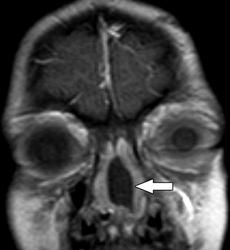

Кисты.